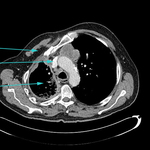

CT scan showing large right pleural effusion

From the collection of Dr Nicholas Maskell; used with permission